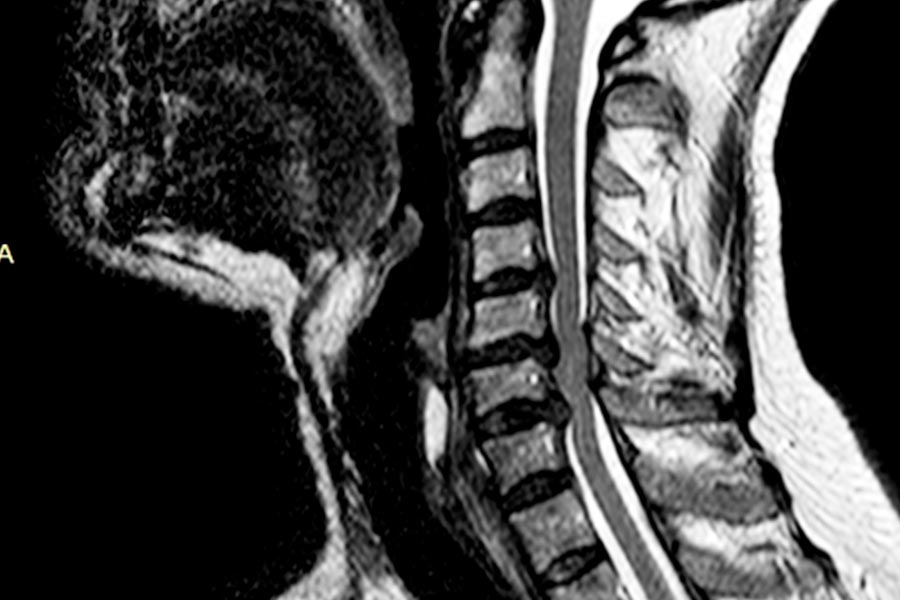

ESPECIALISTA EN MIELOPATIA CERVICAL

Se produce por una estenosis o estrechamiento en el canal cervical de causa adquirida que produce una compresión medular crónica, y esto, a su vez, produce un síndrome clínico caracterizado, en mayor o menor grado, por inestabilidad de la marcha, perdida de destreza en miembros superiores y pérdida del control de esfínteres. El envejecimiento progresivo de la población la MCE se está haciendo muy prevalente.

Aproximadamente el 70% de la población mayor de 65 años presenta evidencia radiológica de patología degenerativa cervical, y un 25% de ellos presentan o presentarán síntomas de compresión medular. El cuadro clínico es muy variable y aunque algunos pacientes pueden, tras unos síntomas iniciales, presentar largos periodos de estabilidad clínica; un número no despreciable (entre el 20 y 60% según las series) presentarán un deterioro progresivo de su función neurológica. Esto conlleva a que en ciertas ocasiones el tratamiento quirúrgico de la mielopatía este indicado.

Galeria Mielopatia Cervical